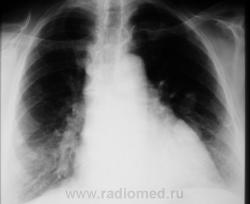

По рентгенографии органов грудной клетки в легких не менее 4 образований... Поскольку живем не в юго-восточной Азии с паразитами, предполагаем в первую очередь метастазы.

Из истории заболевания - оперирована по "женски" чуть больше 1 года назад, получала лучевую терапию....(гинекологи в направлении пишут рак влагалища..